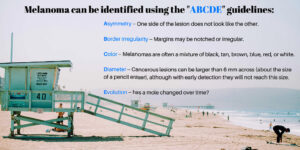

Melanoma Awareness

This year many of us were confined to staying home because of the coronavirus pandemic, and although life may be…